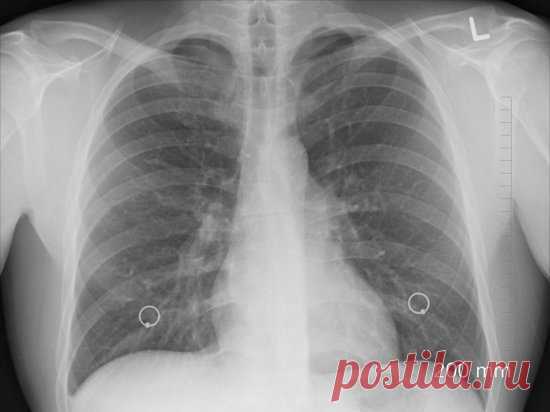

Патологоанатом рассказал о состоянии лёгких больных коронавирусом: